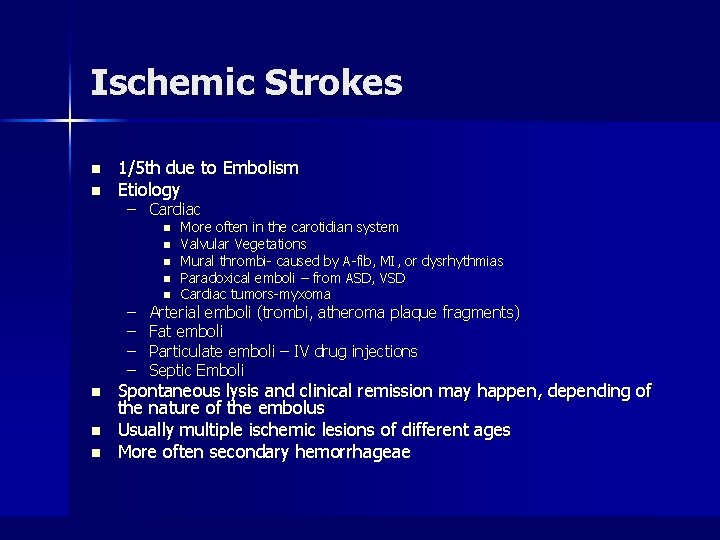

Ischemic Strokes n n 1/5 th due to Embolism Etiology – Cardiac n n – – n n More often in the carotidian system Valvular Vegetations Mural thrombi- caused by A-fib, MI, or dysrhythmias Paradoxical emboli – from ASD, VSD Cardiac tumors-myxoma Arterial emboli (trombi, atheroma plaque fragments) Fat emboli Particulate emboli – IV drug injections Septic Emboli Spontaneous lysis and clinical remission may happen, depending of the nature of the embolus Usually multiple ischemic lesions of different ages More often secondary hemorrhageae